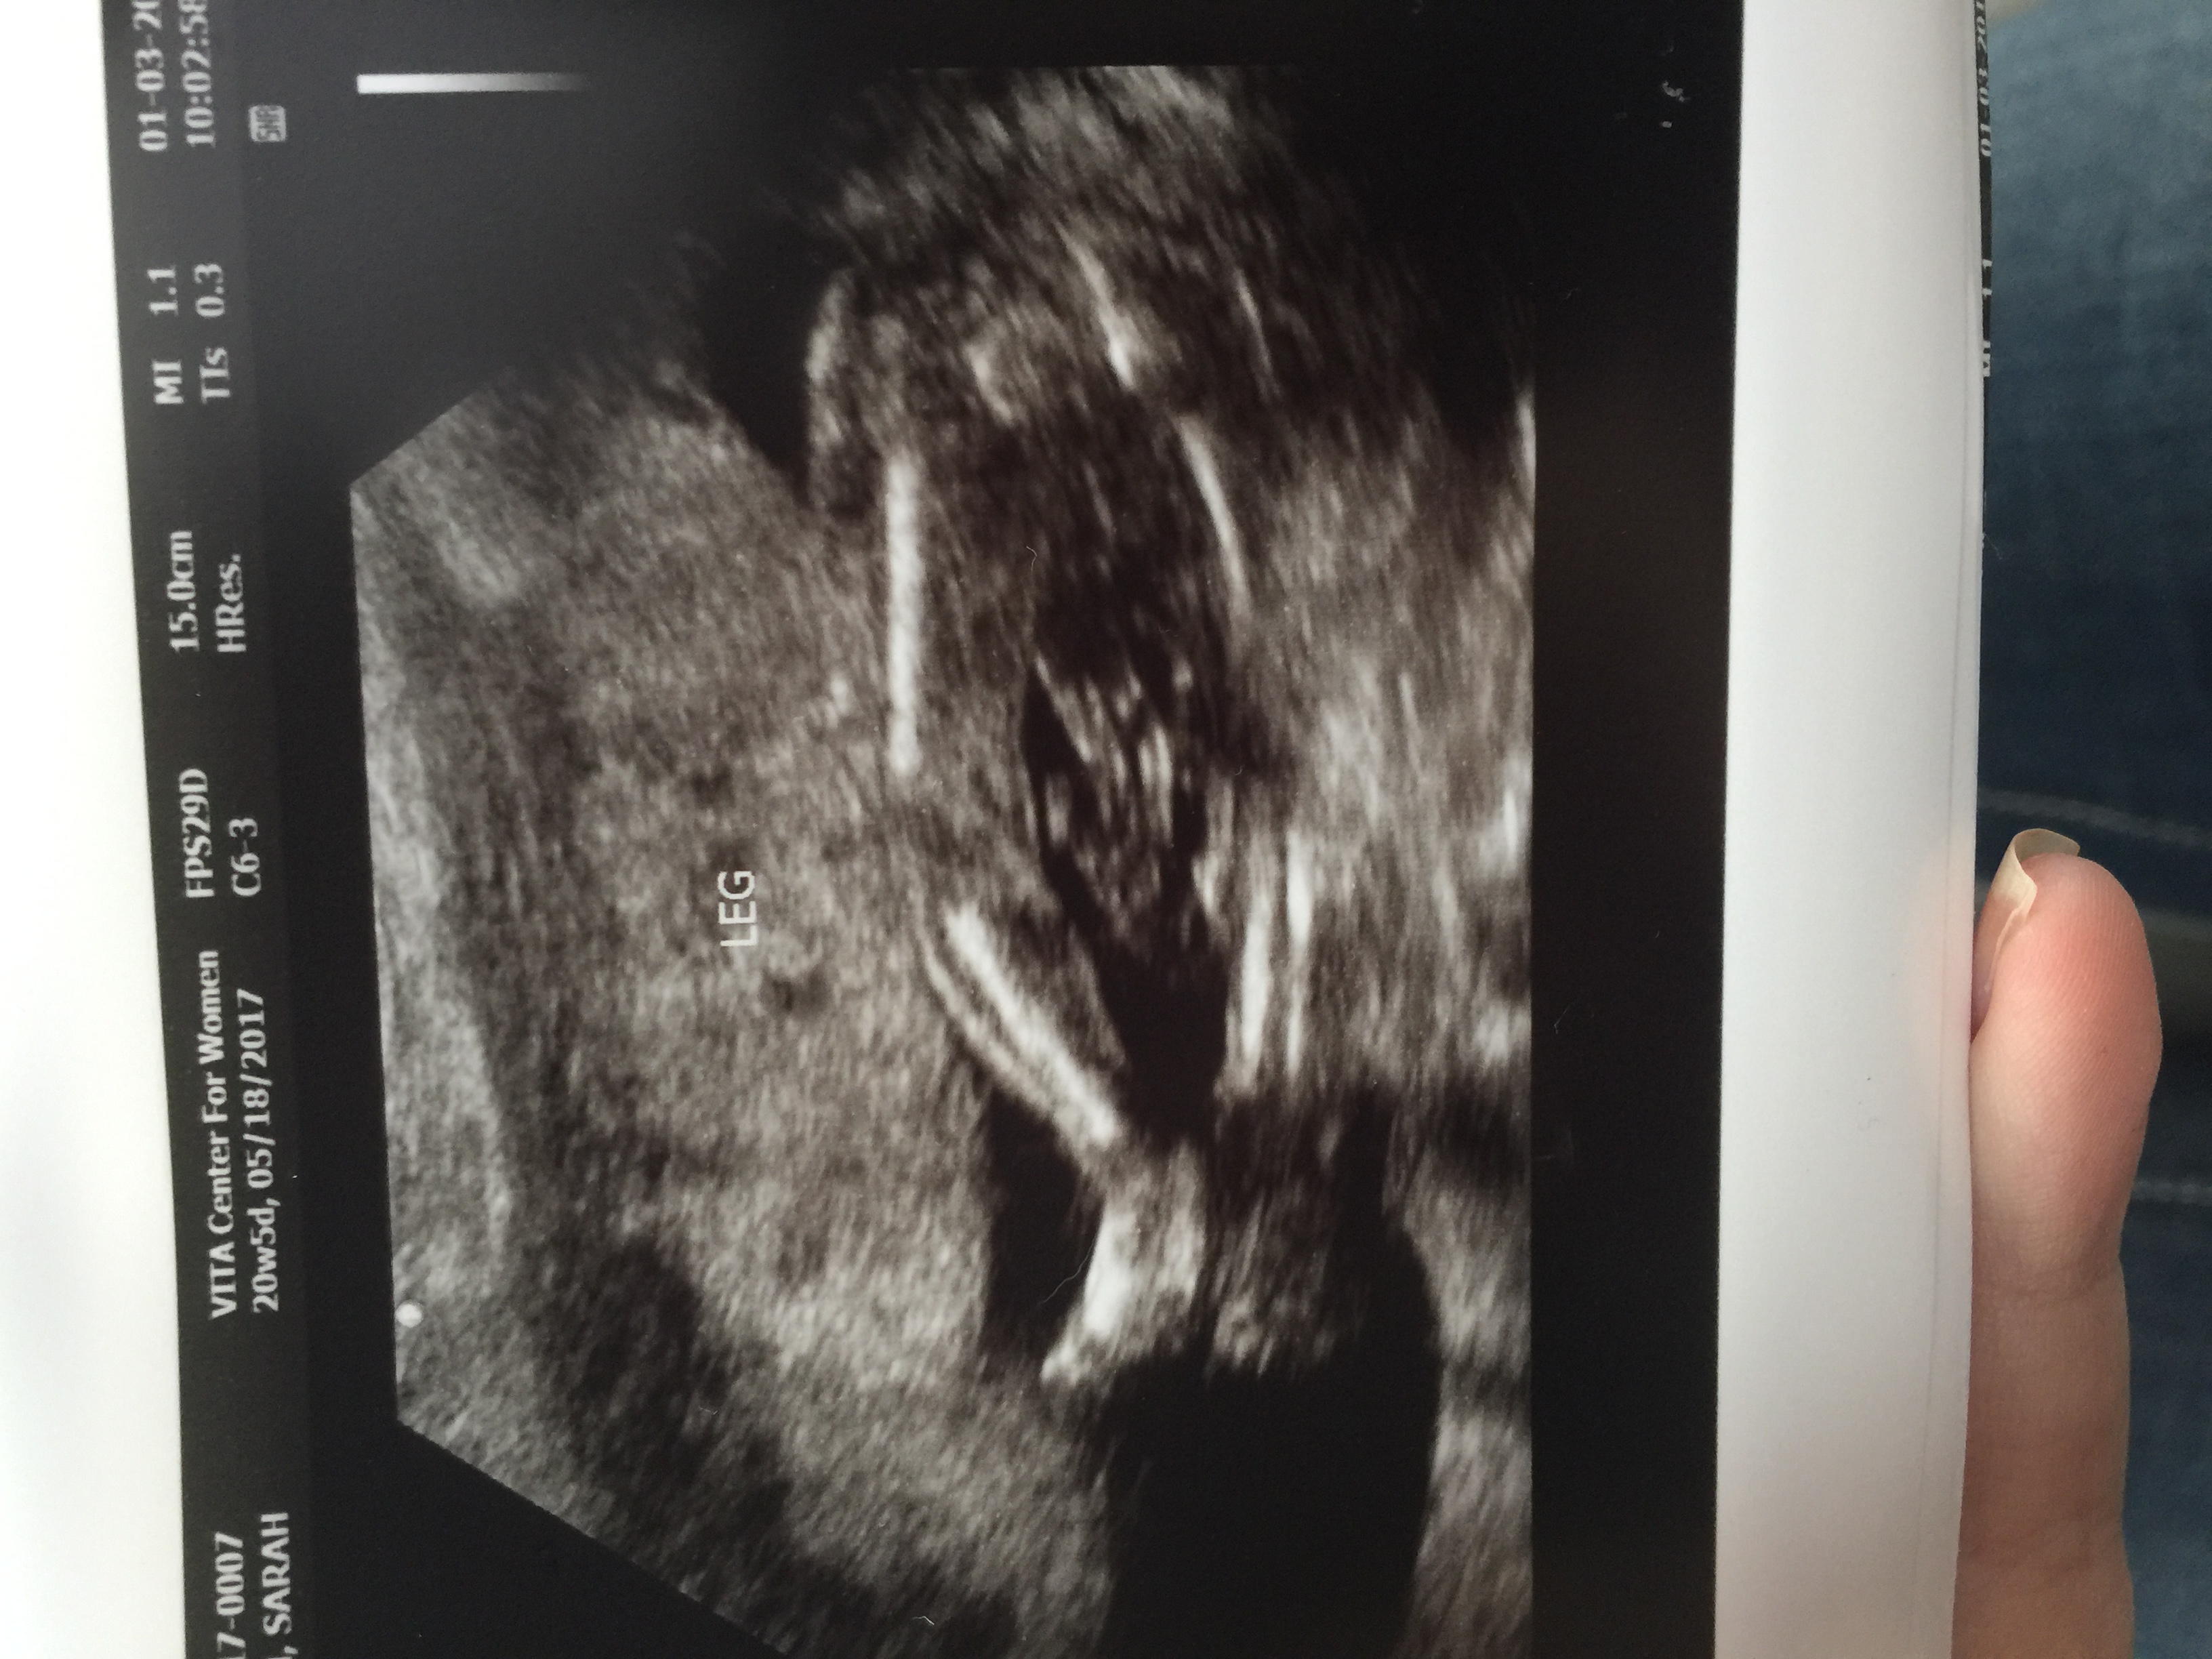

I'm almost 37 weeks and we didn't find out what we are having but it's driving me crazy not knowing. This pic is from right around 20 weeks. What do you think? The cord is in between the legs. The tech did tell me that. Attachment 35921

Honestly with the cord there it's hard to tell either way. I could see this being a girl (three lines) but there's a lot going on between those legs and it's hard to tell if everything that's happening down there is cord. In my experience, if you say you don't want to know they're less likely to send you home with pictures that are easy to tell.